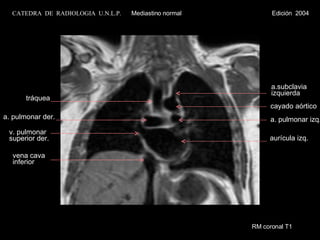

RM coronal T1 vena cava inferior v. pulmonar superior der. a. pulmonar der. tráquea a. pulmonar izq. aurícula izq. a.subclavia  izquierda cayado aórtico CATEDRA  DE  RADIOLOGIA  U.N.L.P.   Mediastino normal  Edición  2004

RM coronal T1vena cava inferior v. pulmonar superior der. a. pulmonar der. tráquea a. pulmonar izq. aurícula izq. a.subclavia izquierda cayado aórtico CATEDRA DE RADIOLOGIA U.N.L.P. Mediastino normal Edición 2004